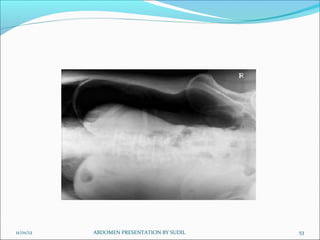

Lateral Decubitus -AP

Lateral decubitus is done instead of abdomen erect if

patient is unable to stand or sit.

Patient position:

 Patient in lateral recumbent position

 Elbows and arms flexed and hand resting near head

 Cassette positioned in vertical bucky against the posterior aspect of the

trunk

Centring of beam:

Equipment setting:

 Note: Patient should be placed in lateral decubitus position for 5-10 mins to

allow the free air to rise

Picture criteria:

 Air fluid levels when an erect abdomen cannot be obtained.

 Lung area above dome of diaphragm

 Lateral abdominal wall and properitoneal fat

 Psoas muscle, lower border of liver and kidney shadows

 No rotation